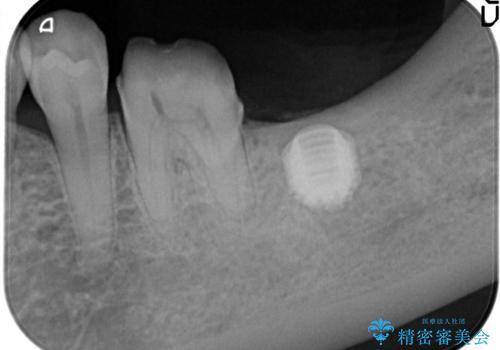

- 左下の1番後方の歯が欠損しており、インプラントにて咬合回復する計画としました。

レントゲン・CT撮影により骨の高さがあまりないことがわかり、ショートインプラントを選択しました。